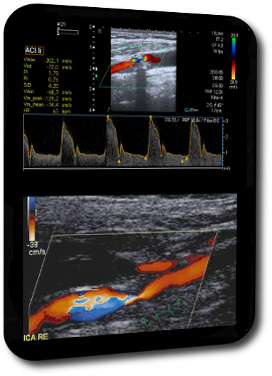

Vaskuläre Erkrankungen

Prof. Dr. Christoph Kleinschnitz

Universitätsklinikum Essen